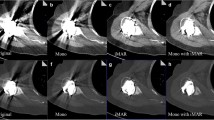

The results of interobserver variability for the relative visual grading score showed good agreement for an overall artifact (κ = 0.75), depiction of soft tissue (κ = 0.62), and cortical bone (κ = 0.61) between the two radiologists. In the pairwise comparison of the three MAR protocols, VMI + PB-MAR showed fewer overall artifacts than did the other two protocols, and when comparing VMI and PB-MAR, PB-MAR was found to have fewer overall artifacts (p < .001). Next, soft tissue was best depicted in the VMI + PB-MAR protocol, followed by PB-MAR in both the femoral and tibial regions (p < .001). For the depiction of cortical bone in the distal femur, PB-MAR showed the best performance, followed by VMI + PB-MAR (p < .001). However, in the tibial stem region, where metal artifacts are relatively small, all three MAR protocols depicted cortical bones to a similar extent (Fig. 3). Representative cases are shown in Figs. 4, 5, and 6.

Axial CT images of the right knee of a 76-year-old woman who underwent total knee arthroplasty surgery on both knee joints reconstructed with the (a) non-MAR, (b) PB-MAR, (c) VMI, and (d) VMI + PB-MAR protocols. All images are shown in the soft tissue window setting (window width = 400 HU, window level = 30 HU). If MAR was not used (a), severe metal artifacts due to large metals cause severe limitations in evaluation, and significant artifacts remained even when VMI was used alone (b). When VMI and PB-MAR were used in combination (d), metal artifacts were reduced the most. VMI, virtual monochromatic imaging; PB-MAR, projection-based metal artifact reduction

Axial CT images of a 77-year-old female patient who underwent total knee arthroplasty surgery of the left knee joint reconstructed with the (a) non-MAR, (b) PB-MAR, (c) VMI, and (d) VMI + PB-MAR protocols. All images are shown in the bone window setting (window width = 2000 HU, window level = 500 HU). If the metal artifacts were not severe, all three MAR protocols reduced artifacts sufficiently, but the metal-bone interface was most apparent for the VMI + PB-MAR protocol. VMI, virtual monochromatic imaging; PB-MAR, projection-based metal artifact reduction

Axial CT images of a 77-year-old female patient who underwent total knee arthroplasty surgery of the left knee joint reconstructed with the (a) non-MAR, (b) PB-MAR, (c) VMI, and (d) VMI + PB-MAR protocols. All images are shown in the bone window setting (window width = 2000 HU, window level = 500 HU). In the case of severe metal artifacts, PB-MAR showed the best performance for the depiction of bone structure (arrow), followed by VMI + PB-MAR protocols. VMI, virtual monochromatic imaging; PB-MAR, projection-based metal artifact reduction